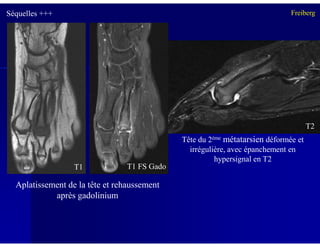

Séquelles +++ Freiberg

Tête du 2ème métatarsien déformée et

irrégulière, avec épanchement en

hypersignal en T2

Aplatissement de la tête et rehaussement

après gadolinium

T1 FS GadoT1